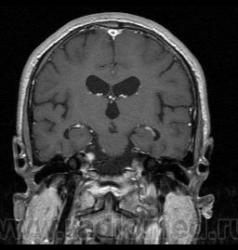

Пациент 35 лет, направлен неврологом из поликлиники с Ds: Рассеянный склероз? У данного пациента в течении года отмечается сильное головокружение и шаткость в походке, пришел на исследование на плечах у родственников. Данное исследование закачено на Dicom-сервер http: //www.radiomed.ru:8080/oviyam/oviyam? (под названием Brain-20101118).

Невринома правого слухового нерва

Если быть точным, VIII нерва;)

Более вероятнее невринома правого слухового нерва.